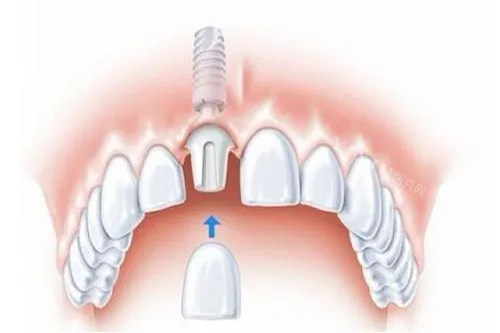

种植牙牙冠崩裂是使用过程中可能出现的问题之一。当牙冠崩裂时,患者往往比较关心的问题之一就是:是否可以免费更换?本文将从多个方面进行详细解析,帮助您更好地了解这一问题。

二、种植牙牙冠崩裂的修复与更换建议

当种植牙的牙冠出现崩裂时,患者应及时就医,以便医生根据具体情况给出修复或更换的建议。以下是一些常见的修复与更换建议:

更换全瓷牙:如果牙冠崩裂的面积较大,或者缺损的位置正好在全瓷牙的边缘,影响美观或功能,医生可能会建议患者更换全瓷牙。